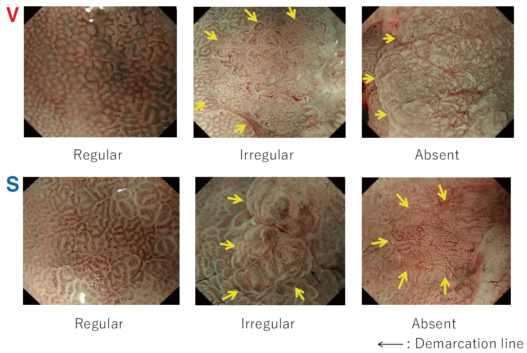

Between the late 1980s and early 1990s, research on image processing and analysis was conducted mainly by the National Cancer Center Hospital East and Olympus Group, which led to basic experiments on narrow band light imaging starting in 1994. As a result, a patent application was made in 1999, and a narrow band imaging (NBI) device (Olympus Co., Tokyo, Japan) was introduced commercially in 2006. Since the early 2000s, it has been demonstrated by a number of researchers that NBI is useful for early diagnosis of cancers of the oropharynx, hypopharynx, esophagus, stomach, and large intestine. A succession of similar techniques was later made public, and interpretation of the term “special light observation” began to differ among academic societies and research organizations. In view of this problem and the need to establish internationally applicable terminology for endoscopy, we proposed an object-oriented classification for endoscopic imaging in 2008. Basically, the concept was that endoscopic imaging can be divided into five categories: (1) conventional endoscopy (white light endoscopy (WLE)), (2) image-enhanced endoscopy (IEE), (3) magnified endoscopy, (4) microscopic endoscopy, and (5) tomographic endoscopy [1].

IEE is subdivided into optical, digital, optical-digital, and chromoendoscopy methods.

While NBI has spread and contributed to the standardization of diagnosis on a global level, our colleagues have worked tirelessly to further improve the quality of endoscopy. Over the last 15 years, owing to the development and worldwide spread of NBI, international classifications have been introduced in the field of gastric cancer, Barrett’s esophagus, and colorectal neoplasia.

Since the introduction of this classification, several IEE techniques have become commercially available through advances in endoscopy technology, including blue light imaging (BLI), linked color imaging (LCI), red dichromatic imaging (RDI), and texture and color enhancement imaging (TXI). Therefore, a revised version including those techniques is presented in Fig. 1.